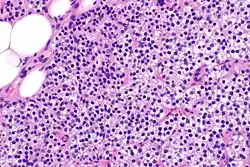

Hyperparathyroidism, in general, is caused by either tumorous growth in one or more parathyroid glands or a prolonged decrease in blood calcium levels or hypocalcaemia which in turn stimulates the production of parathyroid hormone release from the parathyroid gland.[10][11] The parathyroid gland is located beside the thyroid gland in the neck, below and in front of the larynx and above the trachea. It is composed of four glands in total that monitor blood calcium levels via the calcium sensing receptors, a g-coupled protein receptor.[12] The parathyroid glands main role is calcium homeostasis.[13][12] Histologically, these glands are composed of chief cells and oxyphil cells with the chief cell primarily responsible for the storing and release of parathyroid hormone. These cells are arranged in a pseudo-follicular pattern similar to the thyroid follicles. Keratin staining is used to image the parathyroid hormone granules.[9][14]

Primary hyperplasia of the parathyroid gland, results from both hypocalcaemia and increased phosphate levels by decreasing expression of calcium sensing receptors and vitamin D receptors at the parathyroid gland.[8][4] These decreases in receptor expression lead to hyperfunctioning of the parathyroid. Hyperfunction of the parathyroid gland is thought to exacerbate primary hyperplasia which evolves further to a secondary more aggressive hyperplasia. Histologically, these hyperplasic glands can be either diffuse or nodular.[24] Primary hyperplasia, usually resulting in diffuse polyclonal growth is manly related to reversible secondary hyperparathyroidism. Secondary hyperplasia of the parathyroid gland is more often a nodular, monoclonal growth that sustains secondary hyperparathyroidism and is the catalyst in the progression to tertiary hyperparathyroidism. Nodular hyperplastic glands in tertiary hyperparathyroidism are distinctly larger in both absolute size and weight up to 20-40-fold increases have been reported.[25][26][24]

Parathyroid glands are normally composed of chief cells, adipocytes and scattered oxyphil cells.[27][14] Chief cells are thought to be responsible for the production, storage and secretion of parathyroid hormone. These cells appear light and dark with a prominent Golgi body and endoplasmic reticulum. In electron micrographs, secretory vesicles can be seen in and around the Golgi and at the cell membrane. These cells also contain prominent cytoplasmic adipose.[27][14] Upon onset of hyperplasia these cells are described as having a nodular pattern with enlargement of protein synthesis machinery such as the endoplasmic reticulum and Golgi. Increased secretory vesicles are seen and decreased intercellular fat is characteristic.[27][24] Oxyphil cells also appear hyperplasic however, these cells are much less prominent.